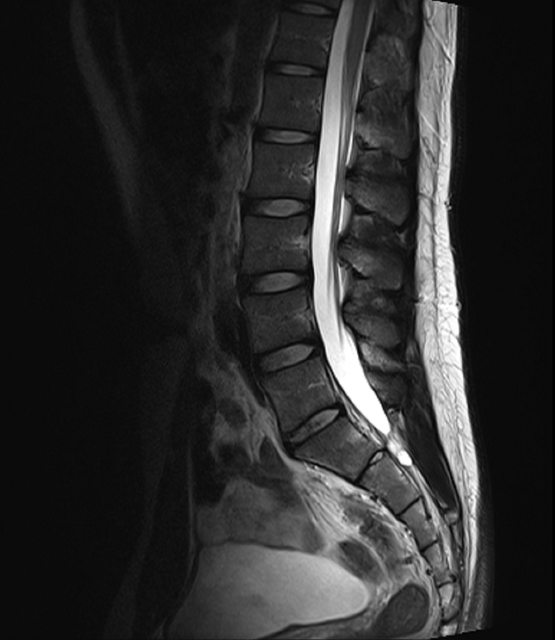

- 胸椎 MRI 正常 - 腰椎 MRI 正常 - Small perineural cysts at S2 level, probably normal variants https://i.imgur.com/QfLxmub.png